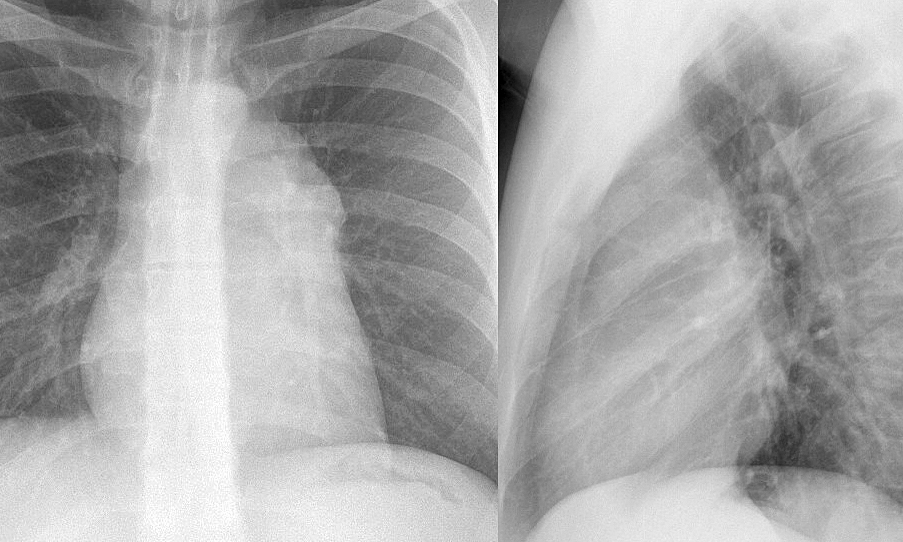

Thymoma